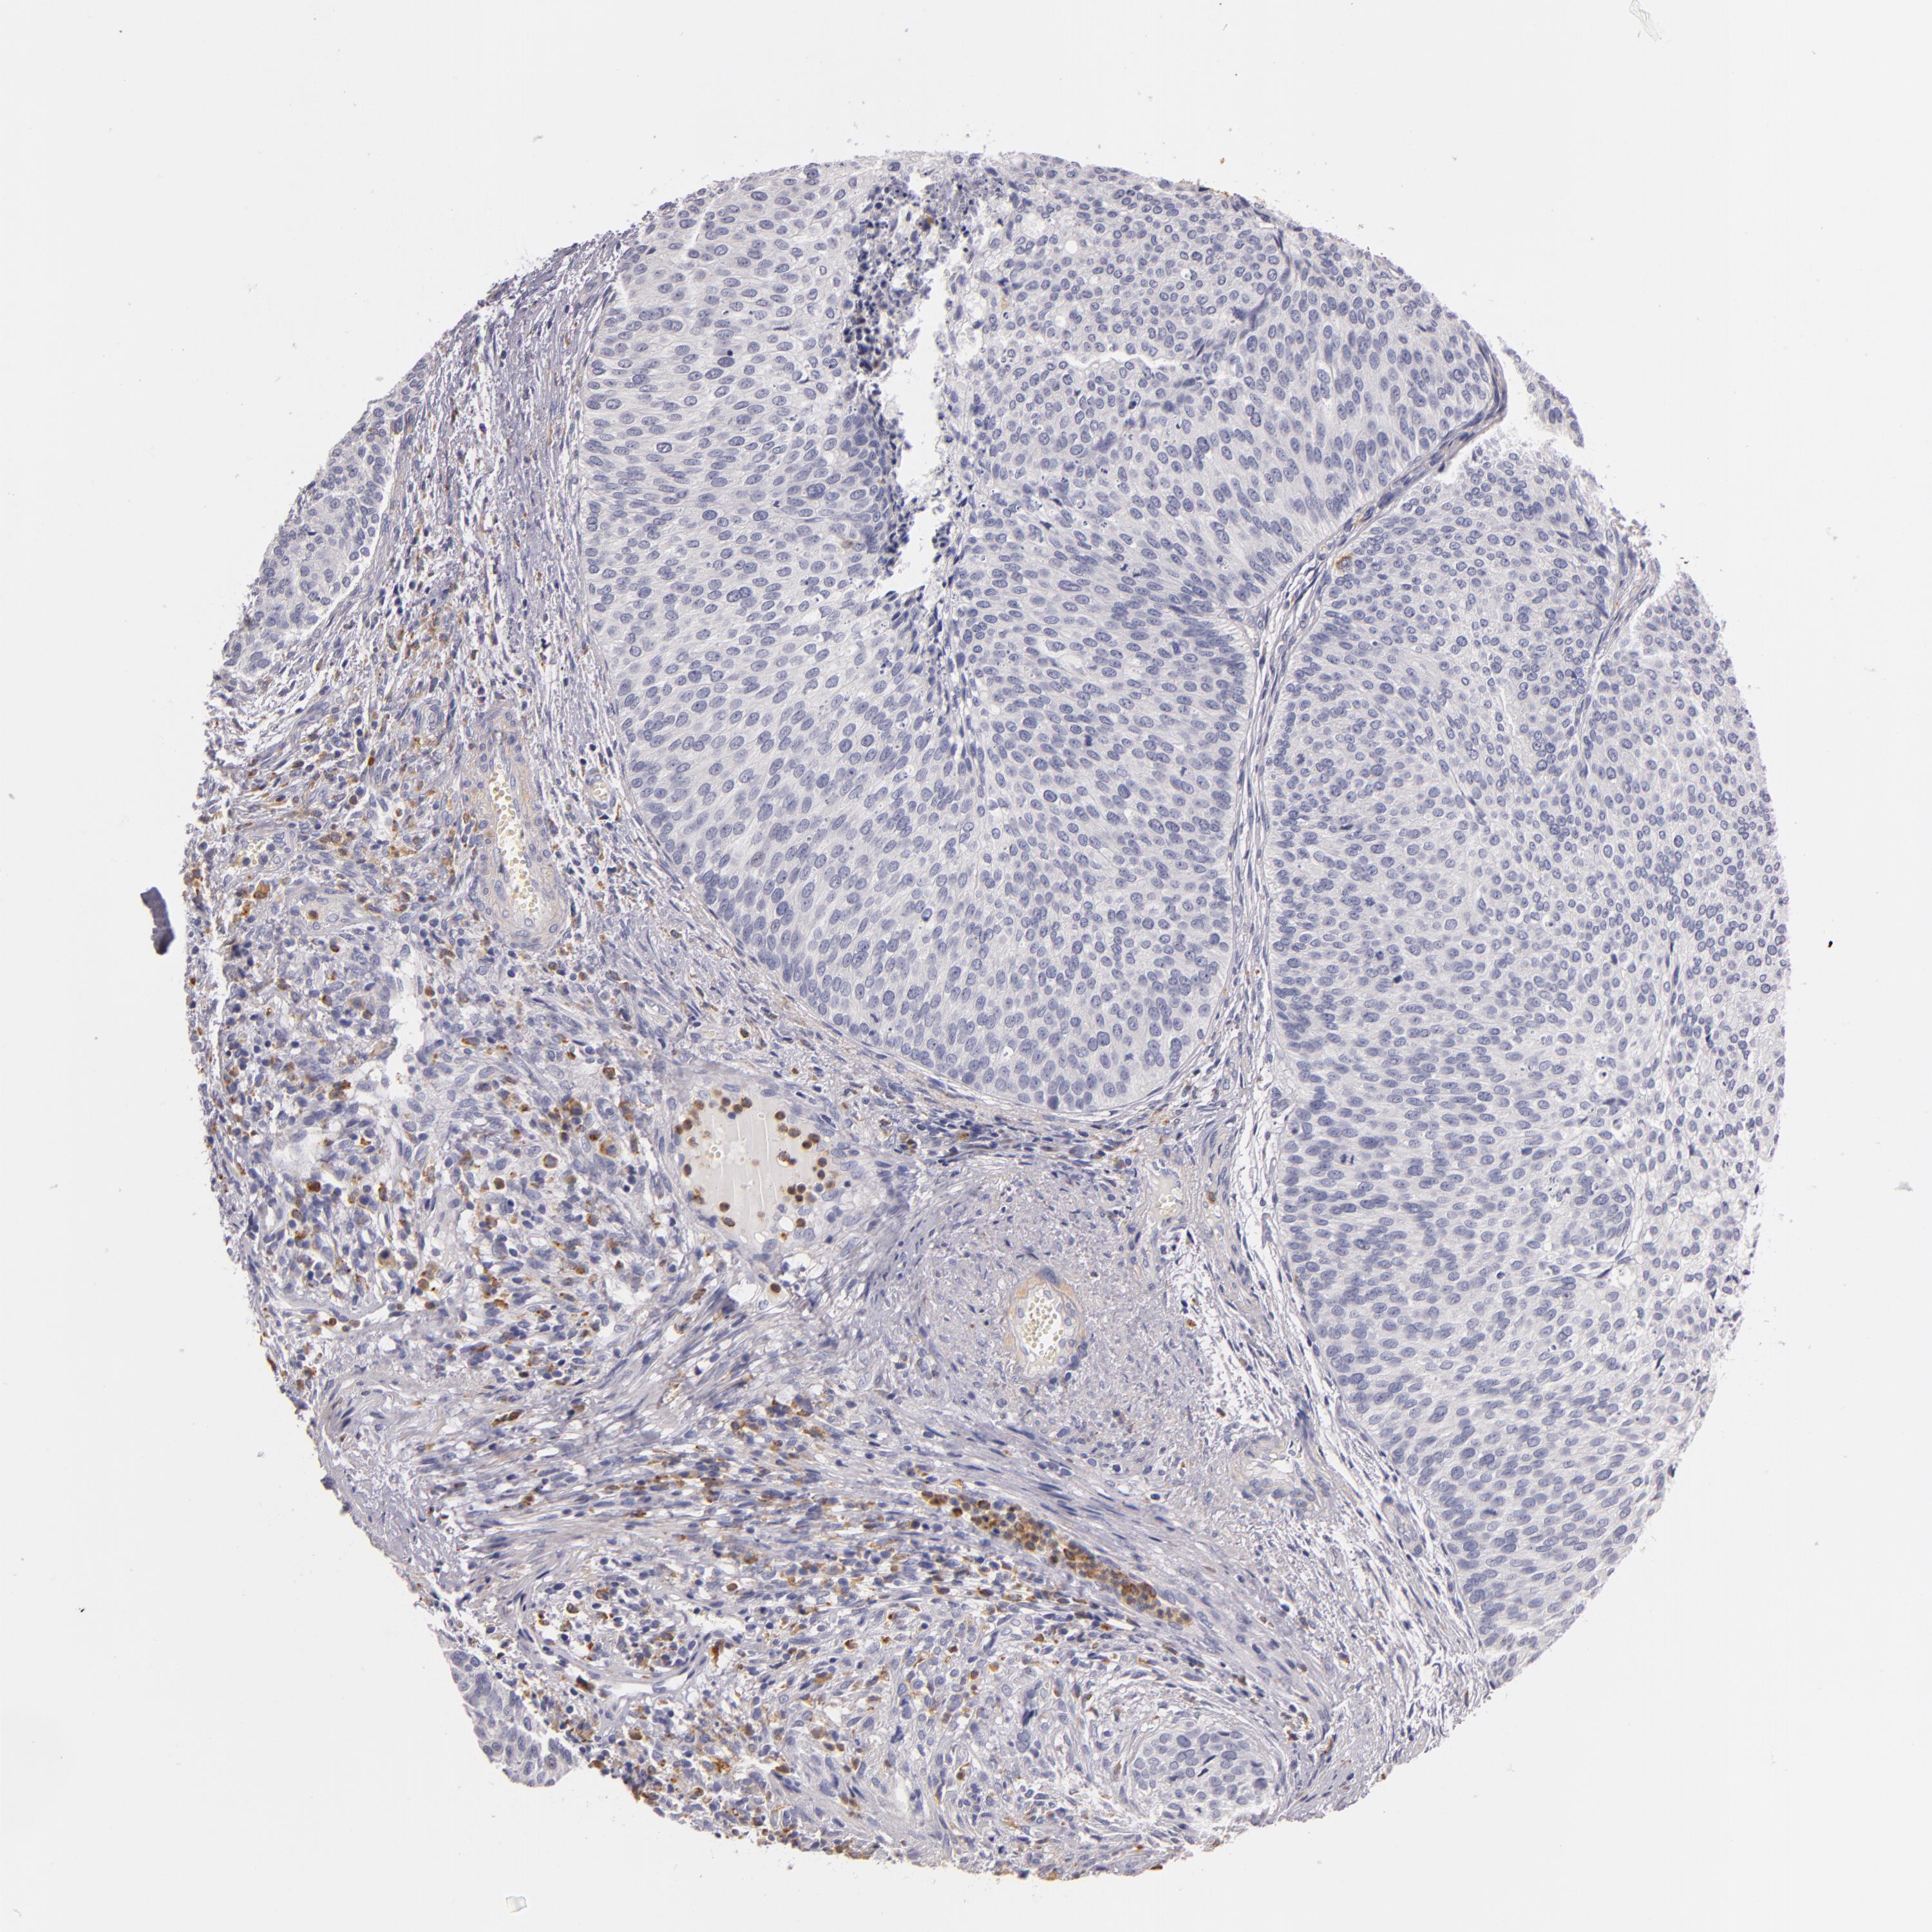

UROTHELIAL CANCER - Protein expressioni

A mouse-over function shows sample information and annotation data. Click on an image to view it in a full screen mode. Samples can be filtered based on level of antibody staining by selecting one or several of the following categories: high, medium, low and not detected. The assay and annotation is described here.

Note that samples used for immunohistochemistry by the Human Protein Atlas do not correspond to samples in the TCGA dataset.

Antibody stainingi

Antibody staining in the annotated cell types in the current human tissue is reported as not detected, low, medium, or high, based on conventional immunohistochemistry profiling in selected tissues. This score is based on the combination of the staining intensity and fraction of stained cells.

Each image is clickable and will lead to virtual microscopy that enables deeper exploration of all samples and also displays staining intensity scores, fraction scores and subcellular localization as well as patient and tissue information for each sample.

Antibody HPA001608

Staining

High

Medium

Low

Not detected

Intensity

Strong

Moderate

Weak

Negative

Quantity

>75%

75%-25%

<25%

None

Location

Nuclear

Cytoplasmic/membranous

Cytoplasmic/membranous,nuclear

Adenocarcinoma, NOS